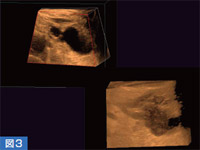

主膵管と交通のある嚢胞は,IPMN(膵管内乳頭粘液性腫瘍),いわゆる前がん病変の可能性が高く,膵がん診断における重要な目安となる。図2では,多房性嚢胞が膵体尾部に認められ,主膵管もわずかに見えているが,交通の有無についてははっきりしない。しかし,MRCPで交通が認められたため,その部分を3Dで確認すると,交通が明瞭に描出された(図3)。

図3